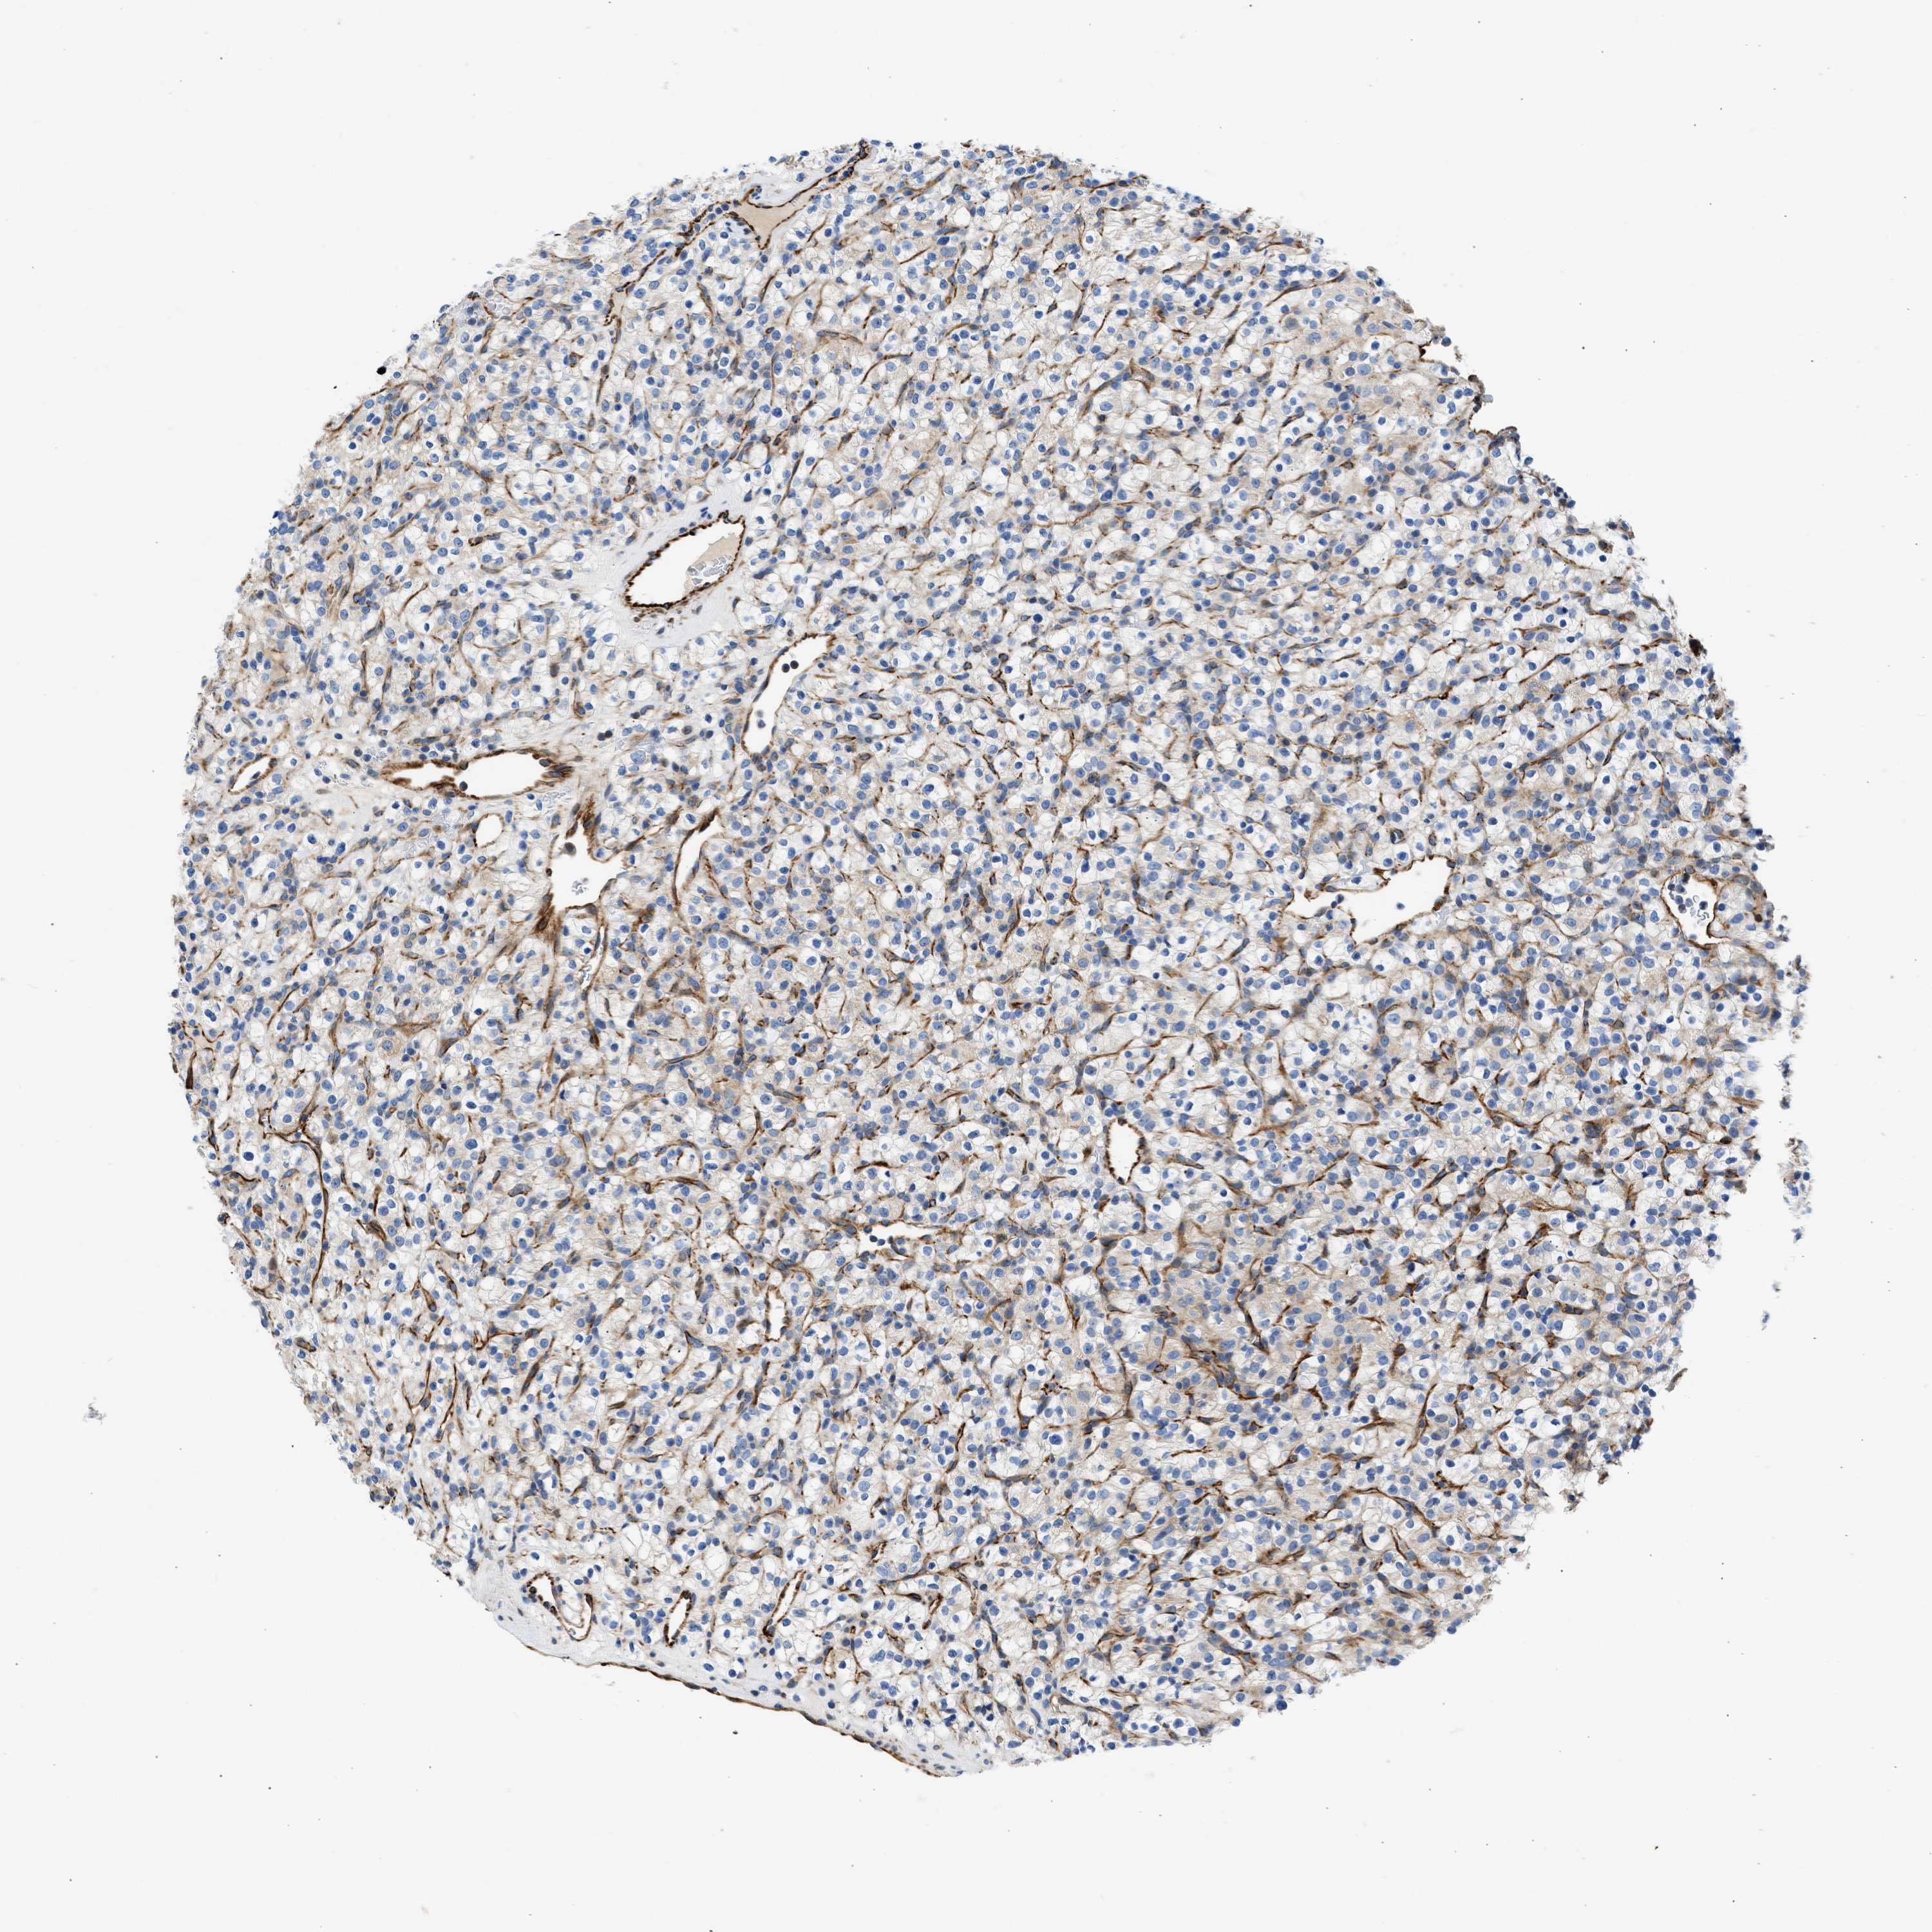

CANCER RENAL CANCER Show tissue menu

KICH TCGA KIRC TCGA KIRC VALIDATION KIRP TCGA PROTEIN RCC CPTAC PROTEIN EXPRESSION

KIDNEY CHROMOPHOBE (TCGA) - Interactive survival scatter ploti

The Survival Scatter plot shows the clinical status (i.e. dead or alive) for all individuals in the patient cohort, based on the same data that underlies the corresponding Kaplan-Meier plots. Patients that are alive at last time for follow-up are shown in blue and patients who have died during the study are shown in red.

The x-axis shows the expression levels (FPKM) of the investigated gene in the tumor tissue at the time of diagnosis. The y-axis shows the follow-up time after diagnosis (years). Both axes are complimented with kernel density curves demonstrating the data density over the axes. The top density plot shows the expression levels (FPKM) distribution among dead (red) and alive patients (blue). The right density plot shows the data density of the survived years of dead patients with high and low expression levels respectively, stratified using the cutoff indicated by the vertical dashed line through the Survival Scatter plot. This cutoff is automatically defined based on the FPKM cutoff that minimizes the p-score. The cutoff can be changed by dragging the vertical line or by entering a cutoff value in the square labeled "Current cut-off".

Under the Survival Scatter plot the p-score landscape (black curve; left axis) is shown together with dead median separation (red curve; right axis). Dead median separation is the difference in median mRNA expression between patients who have died with high and low expression, respectively. It is calculated as follows: median FPKM expression of dead patients with high expression - median FPKM expression of dead patients with low expression. This is intended to aid the user in visually exploring custom cutoffs and the associated p-scores and dead median separation.

Individual patient data is displayed and can be filtered by clicking on one or more of the category buttons on the top of the page. Categories describing expression level and patient information include: high, low, alive, dead, female, male and tumor stages. The scale of the x-axis can be toggled between linear and log-scale by clicking on the "x log" button. Mouse-over function shows TCGA ID, patient information and mRNA expression (FPKM) for each patient.

& Survival analysisi

Kaplan-Meier plots summarize results from analysis of correlation between mRNA expression level and patient survival. Patients were divided based on level of expression into one of the two groups "low" (under cut off) or "high" (over cut off). X-axis shows time for survival (years) and y-axis shows the probability of survival, where 1.0 corresponds to 100 percent.

ULK4 is potential prognostic, high expression is unfavorable in Kidney Chromophobe (TCGA)